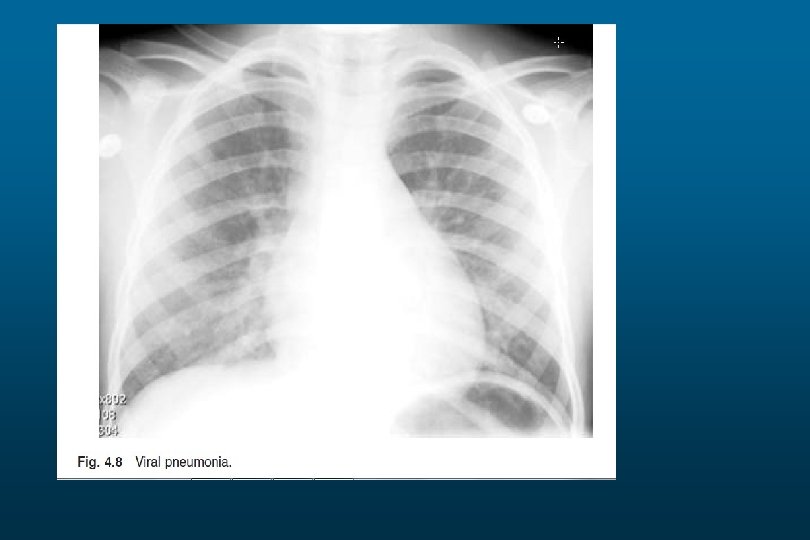

Right Upper Lobe Pneumonia

Right lower Lobe Pneumonia

Left Lower Lobe Pneumonia